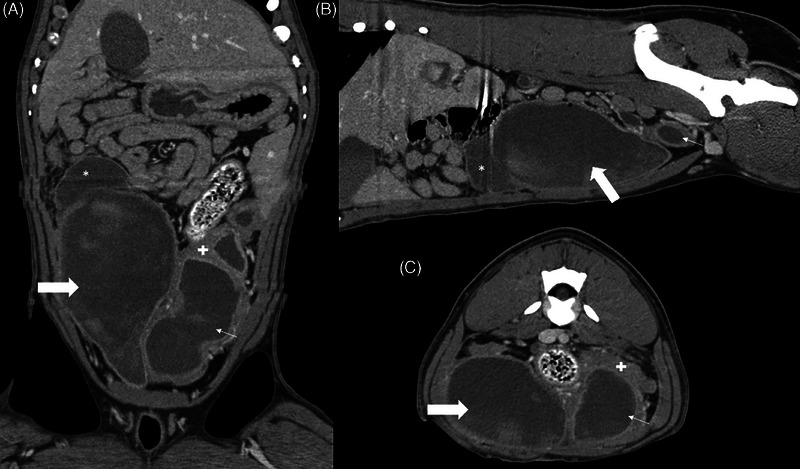

A young, intact, female, American Bulldog was presented for hemorrhagic vaginal discharge. Anemia, thrombocytopenia, leukocytosis with neutrophilia, azotemia, and electrolyte disturbances were detected in the bloodwork. A urachal diverticulum with concurrent uterine distention was identified by ultrasonography and CT. The diverticulum was excised in surgery, and an ovariohysterectomy was performed. Histopathological examination confirmed an abscessed bladder wall with concurrent pyometra.

Abstract Image